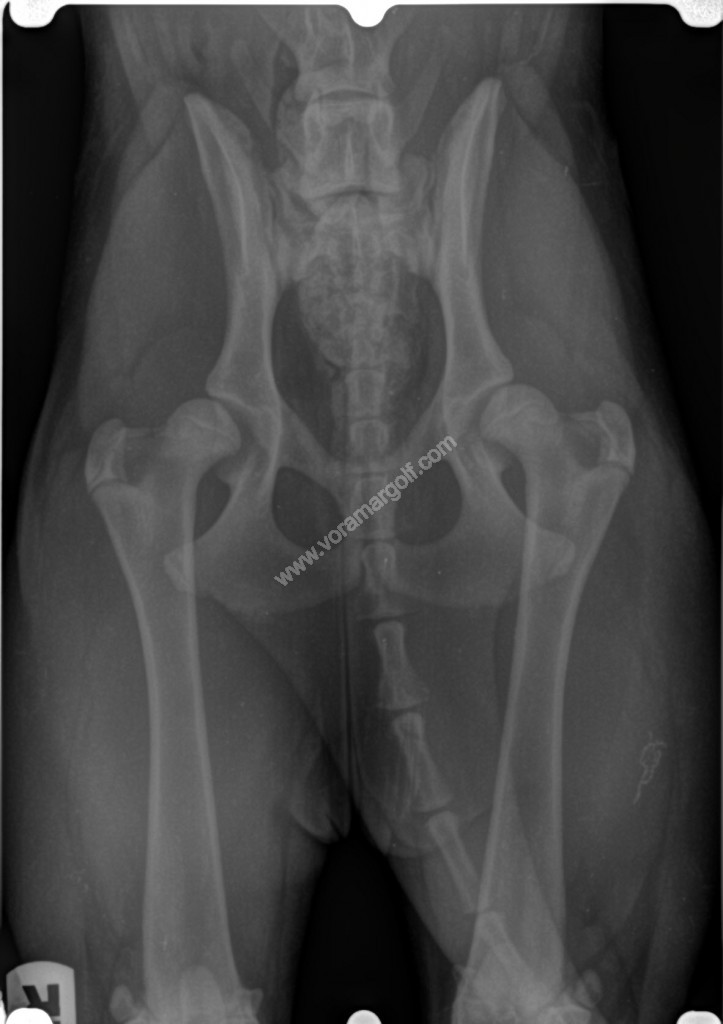

Algunos de los tratamientos más eficaces para la displasia de cadera en perros son: Pérdida de peso. Su objetivo es disminuir el peso del animal con el fin de minimizar el esfuerzo que la cadera ha de soportar. Al reducir el peso del perro, el dolor se verá disminuido y la progresión de la enfermedad se verá frenada. Antiinflamatorios.. Displasia significa malformación durante el desarrollo, por lo que tiende a darse cuando el perro es un cachorro, aproximadamente cuando tiene los 3 a 4 meses de edad y presenta 4 grados de displasia, hoy en día puede presentarse hasta en los gatos. Es muy frecuente en las razas con mucho peso y gran tamaño. Este problema es hereditario por.